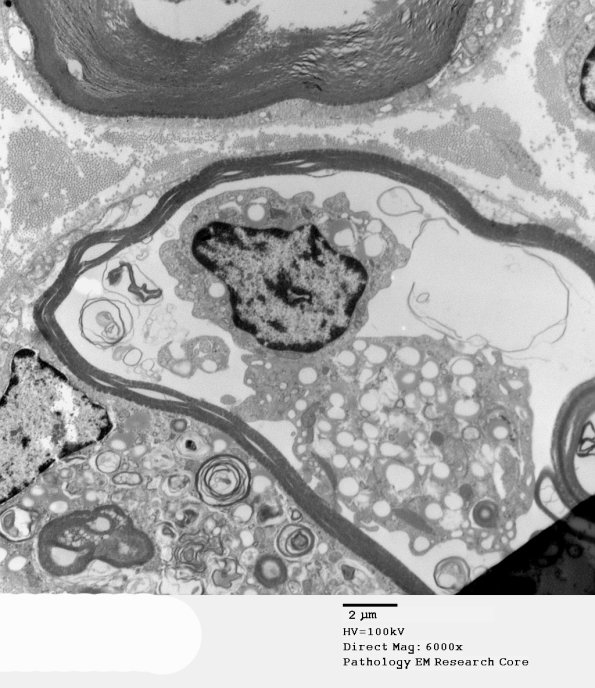

The macrophage is within the myelin sheath which is degenerating as is the adjacent axon. (electron micrographs) ---- Not shown: Teased fiber preparations, although showing no evidence of myelin digestion chambers (associated with axonal degeneration), do show discontinuities in the myelin sheath of some axons.